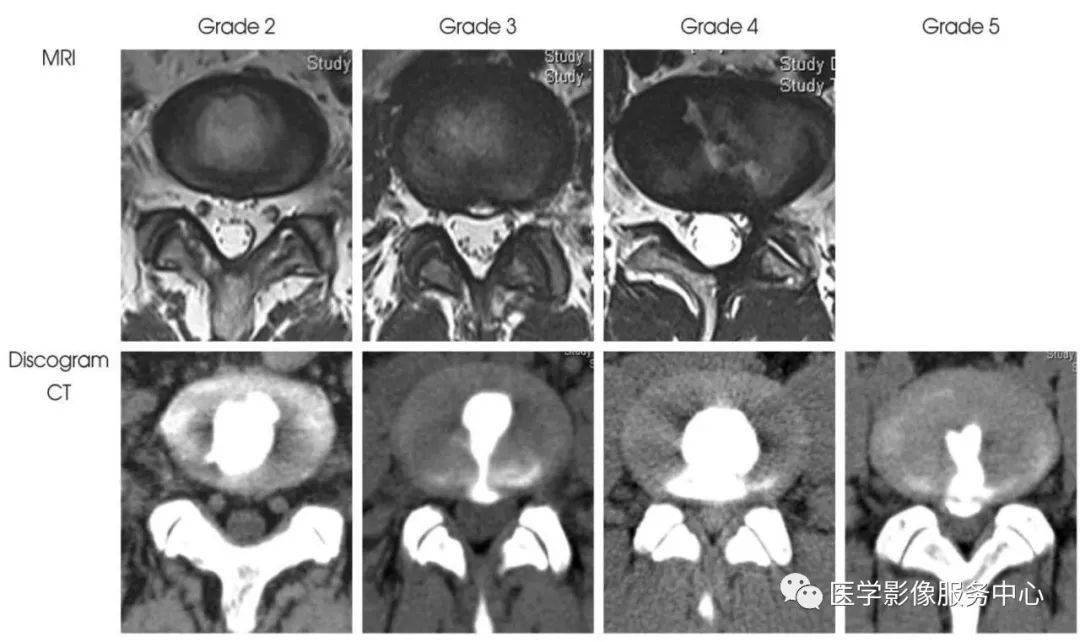

纤维环破裂分级MRI及造影后CT示意图